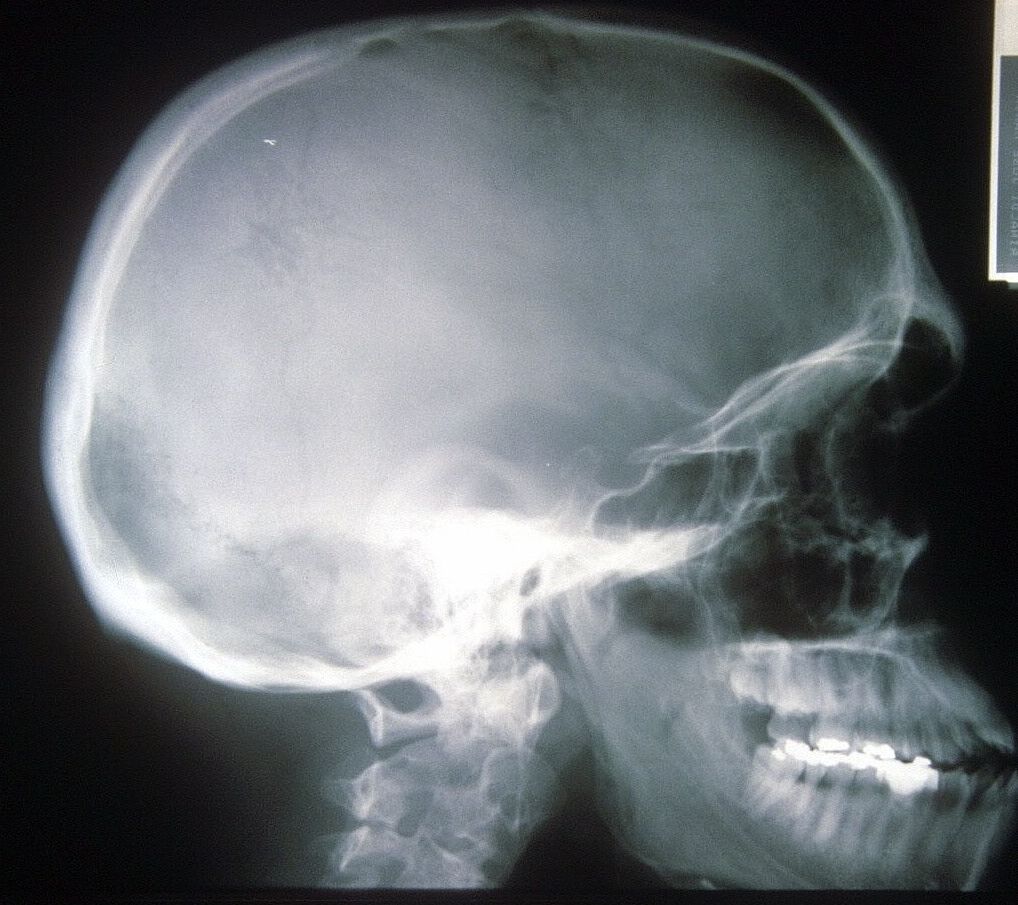

Seudoacondroplasia. [Pseudoachondroplasia]